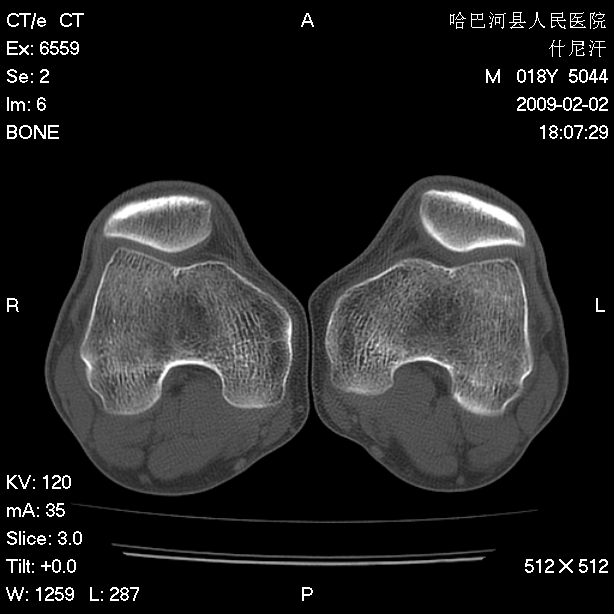

标题: CT17889:外伤后右膝关节反复疼痛3年余 [打印本页]

标题: CT17889:外伤后右膝关节反复疼痛3年余

ct未见明显异常。关节腔未见明显积液,半月板未见明显撕裂。但最好还是mri看看韧带及半月板情况。